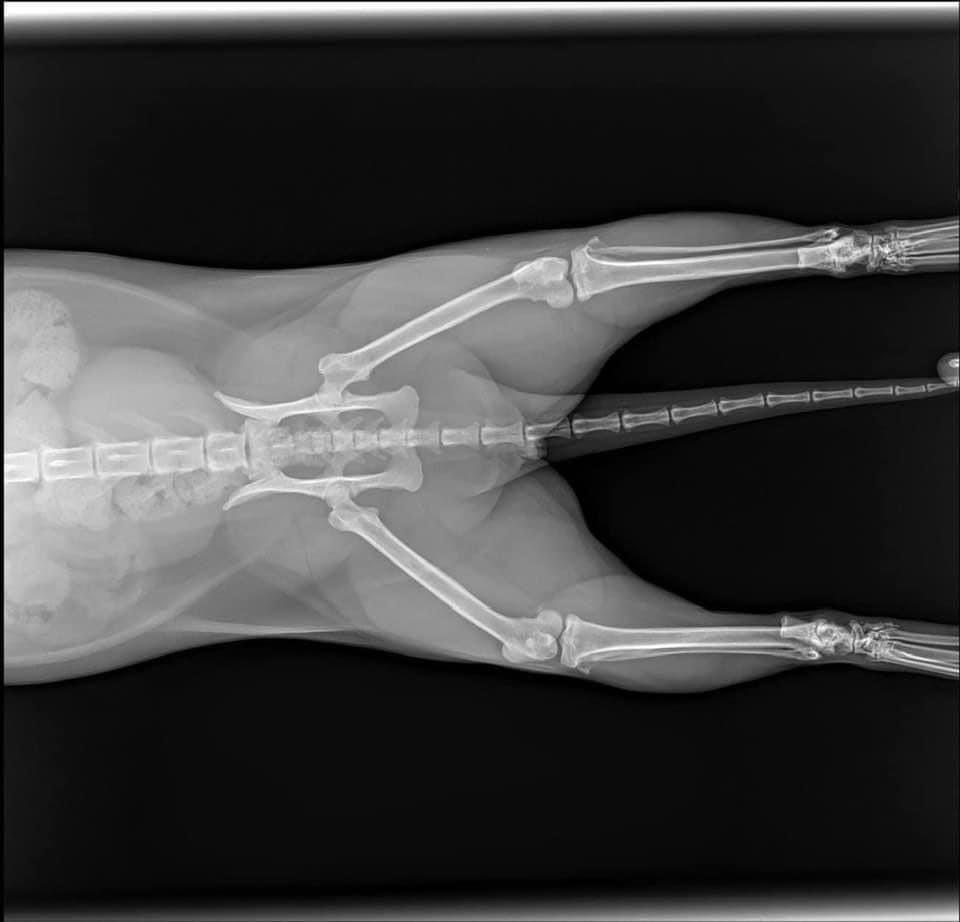

Sáng Chủ nhật đang ngủ ngon lành thì bảo vệ gọi xuống kiểm tra xe, bác còn bảo có con mèo bự làm hư xe, nghe mơ hồ như chiêm bao vậy, cho đến khi xuống xem mới biết. Bà mèo này nặng 8,5kg "hạ phàm" từ trên tầng xuống và làm vỡ kính xe. ![]()

Không chỉ vậy, giờ không tìm ra ai là chủ của nó, nên phải đưa nó đi khám bác sỹ thú y, chụp chiếu các kiểu nhưng may là nó không bị gì, chỉ bị xước 1 tý móng chân, có lẽ do lớp mỡ dày quá chăng?